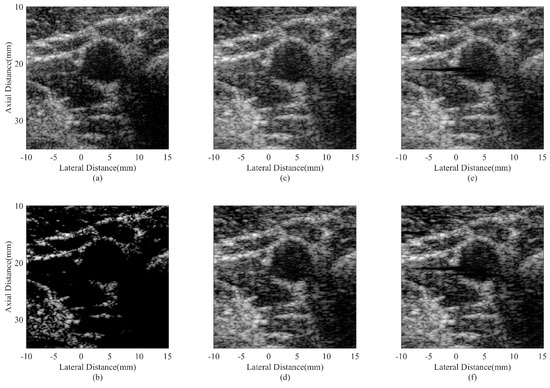

| Beamformer | CR (dB) | CNR |

|---|---|---|

| DAS | 20.19 | 1.57 |

| CF JTR-MV JTR-MV GCF JTR-ESBMV JTR-ESBMV GCF | 59.69 24.50 27.11 25.23 28.03 | 0.89 1.60 1.55 1.61 1.56 |